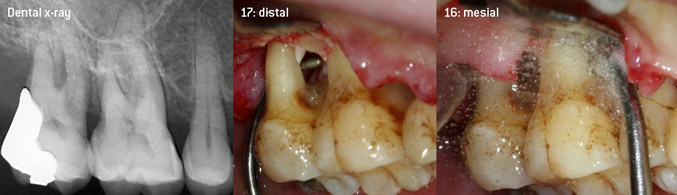

L'idea era di sviluppare una punta applicabile universale al fine di evitare le sostituzioni della punta, per cui era richiesto parecchio tempo. Inoltre, si doveva facilitare l'utilizzo delle nuove punte in tasche intraossee strette dalla parte distale e all'entrata della forcazione distale dei molari mascellari, per consentire così un utilizzo più efficace degli strumenti. Ciò è stato possibile adottando una curva dello strumento con un diametro più ampio (figura 1), un vantaggio enorme in particolare per il debridement chiuso sui denti con perdita avanzata degli attacchi e dove entra in gioco la forcazione (figura 4).

debridement chiuso della forcazione sul dente 16

Fig. 4: debridement chiuso della forcazione sul dente 16 con perdita avanzata di attacchi